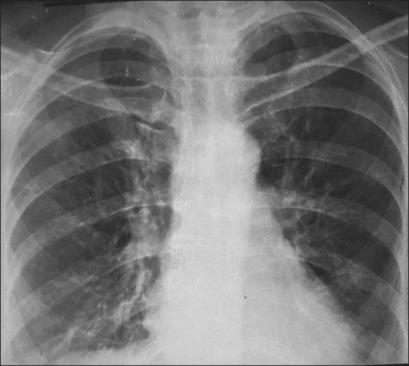

Sarcoidosis presenting in a human immunodeficiency virus patient before starting antiretroviral therapy - "Granuloma paradox".